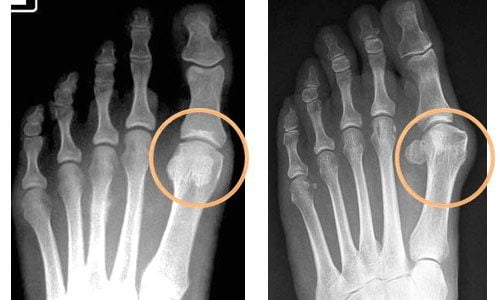

Определяющим критерием стадии артрита являются рентгенологические признаки. На начальных этапах развития какие-либо изменения отсутствуют. На второй стадии наблюдается разрушение гиалиновых хрящей, на третьей — подвывихи мелких суставов. Для артрита высокой степени тяжести (4 стадия) характерно полное или частичное сращение костных поверхностей.

В диагностике артрита наиболее информативны рентгенография, УЗИ, магнитно-резонансная и компьютерная томография.

- разрушение хрящей;

- деформацию костных структур;

- локализацию и степень воспаления.

Диагностические мероприятия также помогают исключить плантарный фасциит, подпяточный бурсит, болезнь Мортона.